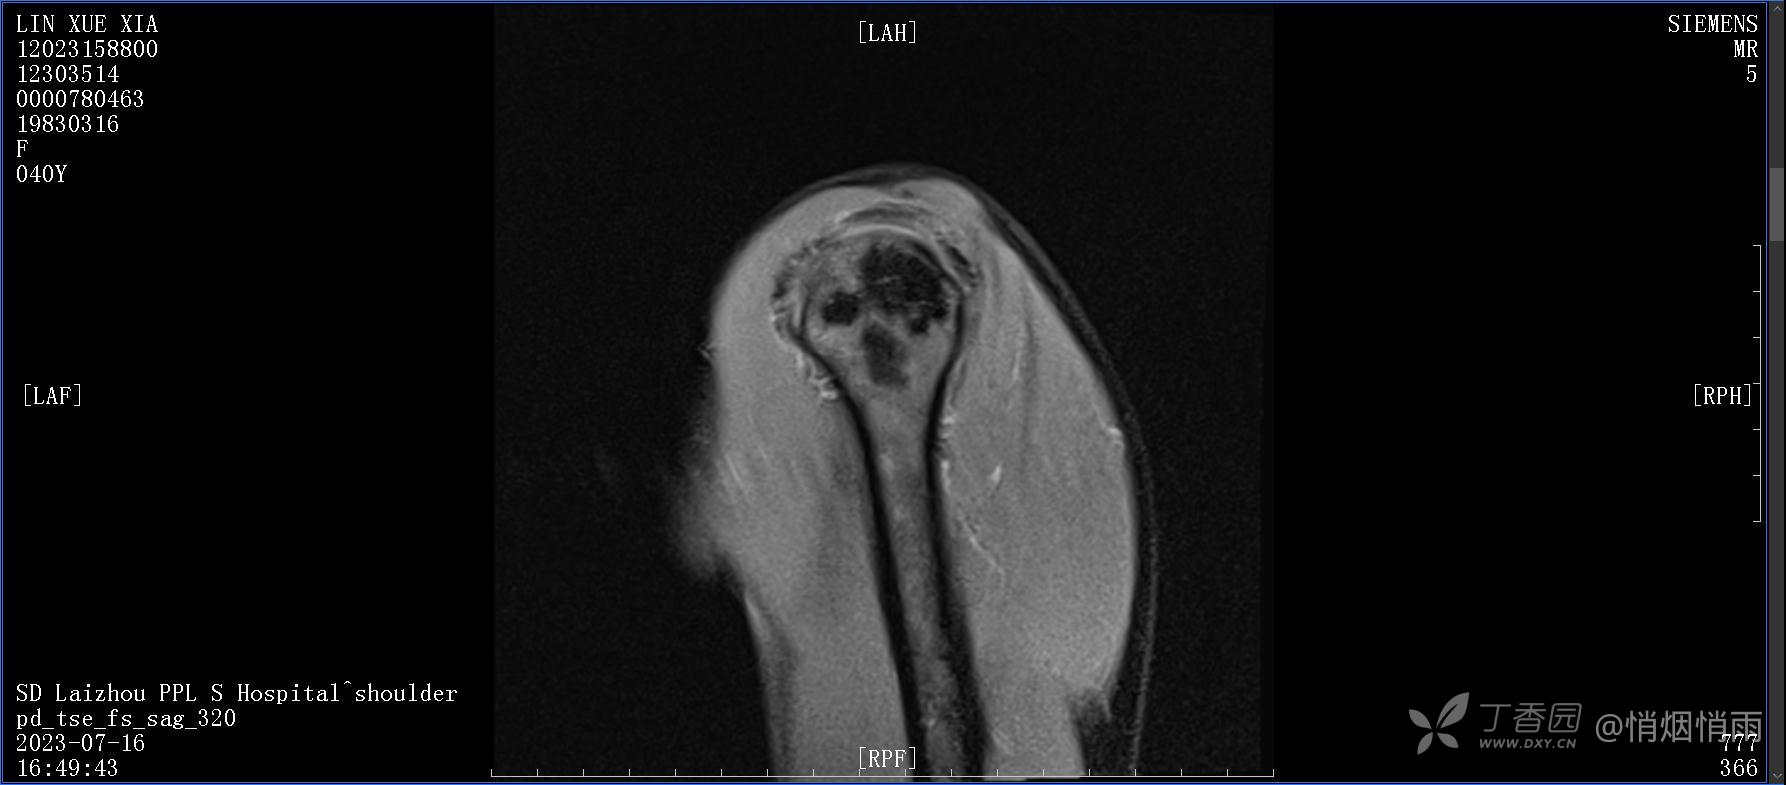

查体:右肩关节局部轻度肿胀,肩胛区压痛明显,痛处不固定,肩关节痛性活动受限,jobe test(+),lift -off test(+),中指、环指感觉较余指减退,余肢端感觉及血运情况可。

目前的诊断,暂时依据辅助检查诊为肩袖损伤,但是患者疼痛的性质和特点,却不是单纯的肩袖损伤所致。考虑过胸廓出口综合征,但是该疾病会出现肩胛区的疼痛吗?(由于考虑到费用的问题,没再进行下一步的检查)带状疱疹会有如此的症状吗?